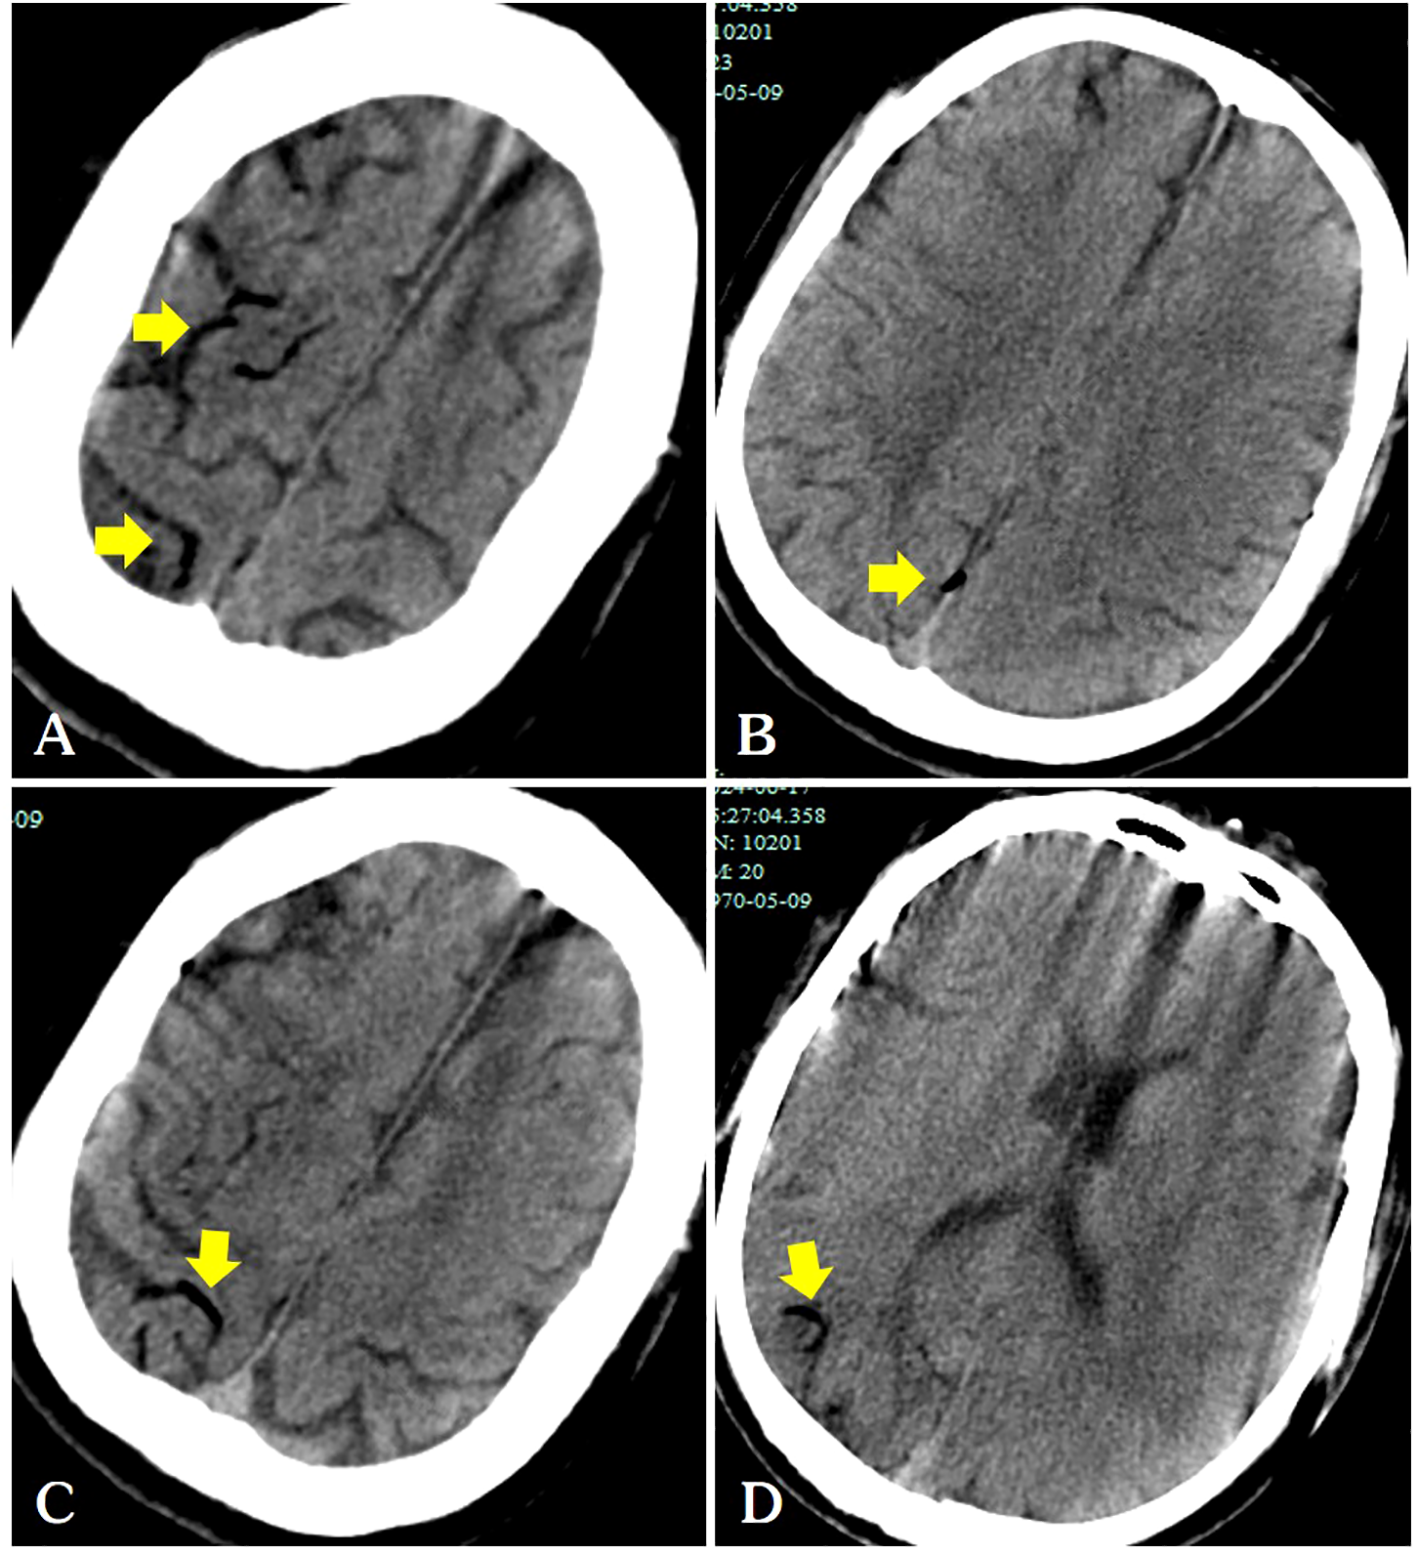

Figure 3

Following the patient’s recovery of breathing and heartbeat, a head CT scan revealed air within the cerebral veins (A–D, arrows).

In our case, air was observed in the surface veins of the cerebral sulcus and sagittal sinus on the patient’s head CT, and a diagnosis of venous cerebral infarction was confirmed on head MRI a few days later. A detailed preoperative examination ruled out a left-to-right cardiac shunt. Air in the pleural cavity may have indirectly enters the pulmonary arteries through the puncture needle track. The mechanism of retrograde cerebral venous air embolism was further supported by the presence of air in the right atrium on chest CT images (Figure 2C). The occurrence of venous cerebral air emboli may be attributed to the retrograde movement of air into the jugular veins, particularly in instances where the patient is in an upright position. Intravenous gas may travel through the veins in a direction opposite to the normal blood flow and reach the intracranial venous sinuses if the volume of the air embolus exceeds the capacity of the pulmonary filter (4).